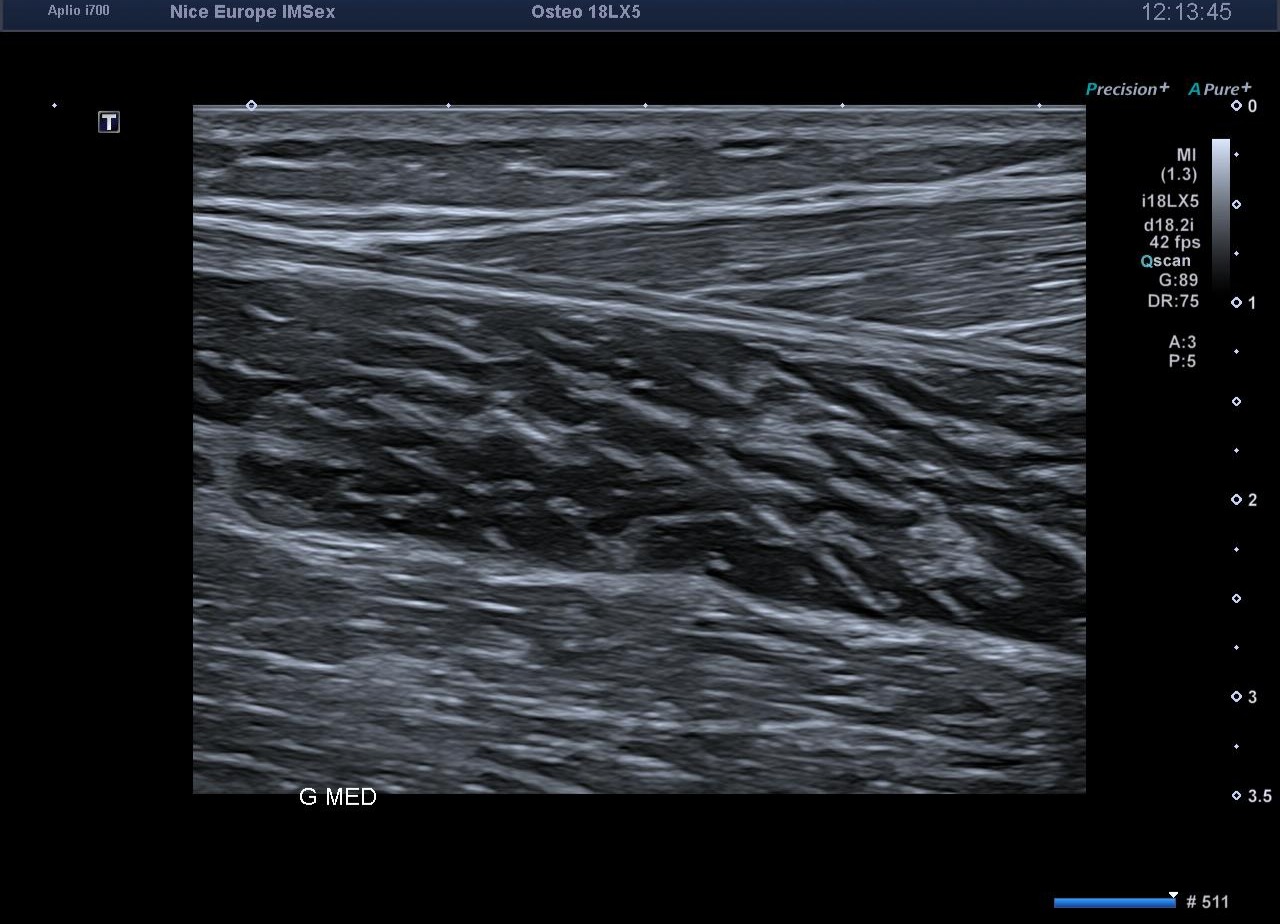

L’exploration statique haute résolution de la cheville et du mollet s'avère strictement normale. Les tendons calcanéens (d'Achille) présentent une écho-structure fibrillaire parfaitement conservée, sans épaississement focal, ni hyperhémie au Doppler énergie. L'exploration de la loge postérieure montre des ventres musculaires gastrocnémiens et soléaires volumineux mais d'échostructure normale, tout comme les jonctions myo-aponévrotiques. L'artère poplitée est perméable au repos, avec un flux Doppler triphasique physiologique.

À ce stade, l'examen clinique, obligatoirement réalisé de manière concomitante à l'exploration échographique, prend tout son sens. La palpation minutieuse des loges musculaires et la parfaite intégrité des tendons obligent l'opérateur à s'écarter de la prescription initiale pour rechercher une étiologie vasculaire à cette symptomatologie d'effort.